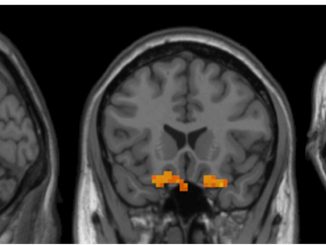

Researchers identify differences in spontaneous brain activity in people with Down syndrome

12.13.2022

Researchers of the Faculty of Psychology, the Institute of Neurosciences (UBNeuro) and the Institute of Complex Systems (UBICS) of the […]